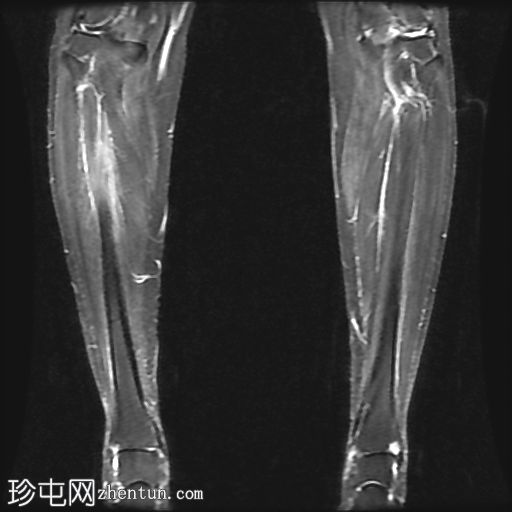

冠状位

STIR序列

多发局灶性皮质内T2/STIR高信号病灶。皮质内可见一条线状信号异常区域。

邻近髓腔内广泛的骨髓水肿。

胫骨内侧缘骨膜水肿。

高等级内侧胫骨应力综合征(4b 级)表现为皮质内线性骨折线,伴有广泛的骨髓和骨膜水肿,代表皮质突破前的高级应力反应。

关键要点:4b 级骨折的定义是皮质内线性信号异常加上骨髓和骨膜水肿——MRI 对于诊断和防止发展为完全性骨折至关重要。